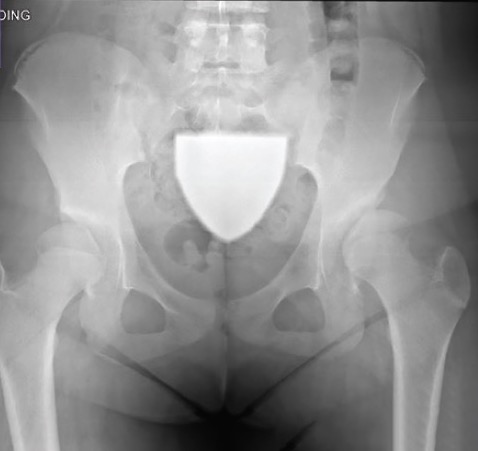

Photoclinic

05/25/2022

A 12-year-old girl presented to with left-sided hip pain and a limp that had been progressively worsening over the past 8 months.